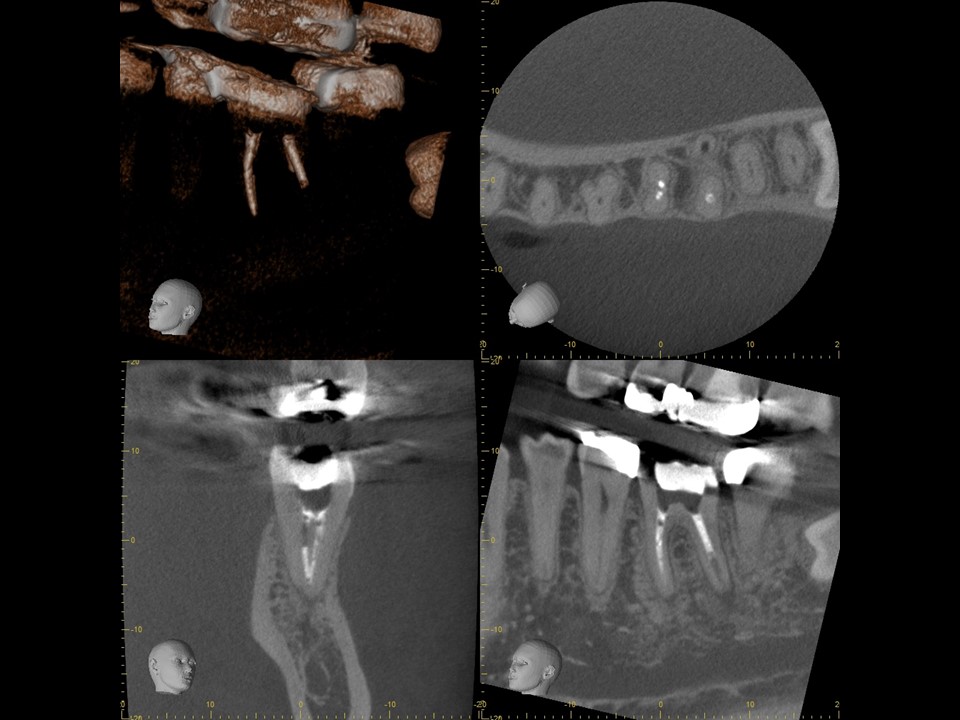

同CT画像。ファイバーコアで土台を補強し、仮歯の状態で3か月の経過観察を行った。初診時にあった歯の違和感は完全に消失したため、オールセラミックで補綴処置を行うこととした。